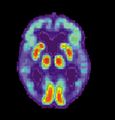

مسح PET لمخ غير مصاب - الصورة مقدمة من مركز الإحالة والتوعية بمرض ألزايمر التابع للمعهد الوطني للشيخوخة بالولايات المتحدة.

مسح PET لمخ مصاب بمرض ألزايمر - الصورة مقدمة من مركز الإحالة والتوعية بمرض ألزايمر التابع للمعهد الوطني للشيخوخة بالولايات المتحدة.